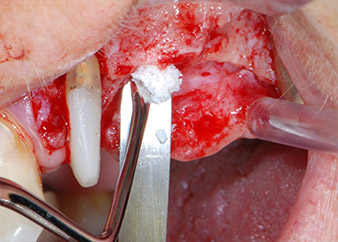

Въпреки това, ние се придържахме към първоначалния си план да запазим и двата зъба като абатмънти за временен мост по време на 6-месечната остеоинтеграция на имплантите. При повторна интервенция, ситуацията трябва да се преразгледа. Първо, в опит да се овладее ендо-перио проблема, останалата повърхност на зъба е внимателно обработена с пиезохирургично оборудване (Piezomed, W&H, използван с накрайник S1 под формата на шпатула, първоначално проектиран за ерозия на латералната синусна стена) (Фиг. 4).

Фиг. 4: За да се съхрани зъбът като временен абатмънт, периодонциумът е изпилен с пиезохирургично оборудване...